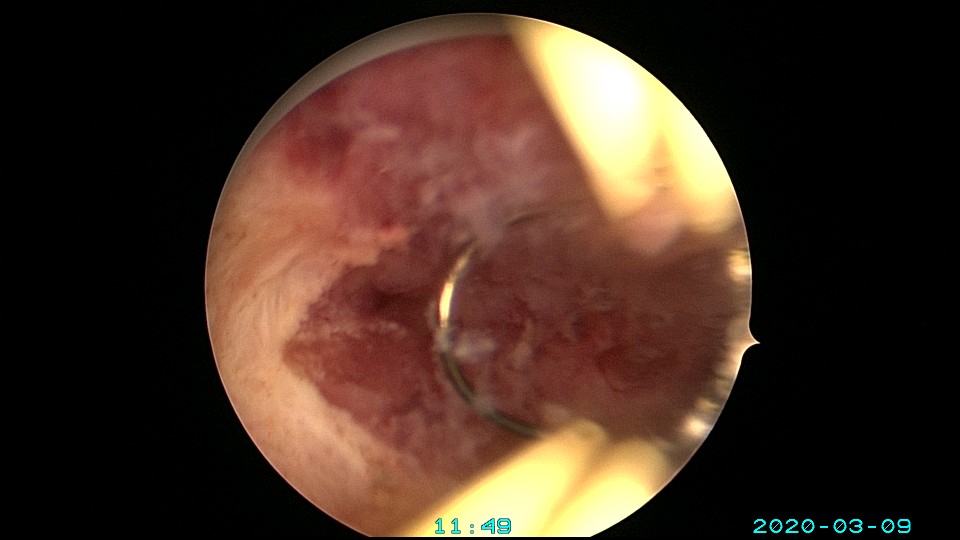

患者36岁,G3P0,自然流产3次,发现宫腔粘连3个月。2020年3月宫腔镜探查,子宫前倾后屈位,宫深8.5cm,宫颈管粘连狭窄,扩宫进入宫腔,见宫腔中下段两侧壁粘连,剪刀及双极电切分粘,宫腔形态恢复正常,双侧输卵管开口显露。2020年4月宫腔镜二探取球囊,宫腔形态正常,双侧输卵管开口可见。2021年6月自然妊娠,2022年2月足月剖宫产分娩。现42岁,G4P1。